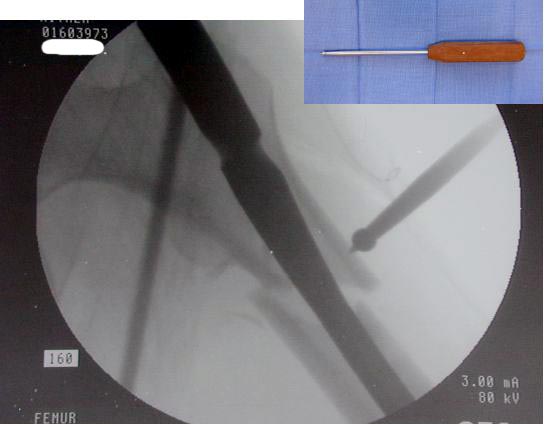

Деформирующие силы усложняют закрытую репозицию и фиксацию Перед операцией КТ для определения степени вовлечения пириформис фосса.

Большие преимущества у интрамедуллярных штифтов, метод хорош и можно произвести из минимального доступа, но во время операции необходимо контролирование варуса, затем приступить к блокированию.

Для молодых больных выбрал бы тактику fixed angled device 95 degree Blade Plate, техника непрямого метода репозиции, который описал в своей книге Jeff Mast, Planning and Reduction Technique in Fracture Surgery ( method of Inderect Reduction), репозиция и фиксация происходит за счет фиксации головки бедра к femoral shaft с помощью пластины, а что в середине должны репонироваться без больших усилии и без разрушения мягкотканого соединения c медиальной стороны.